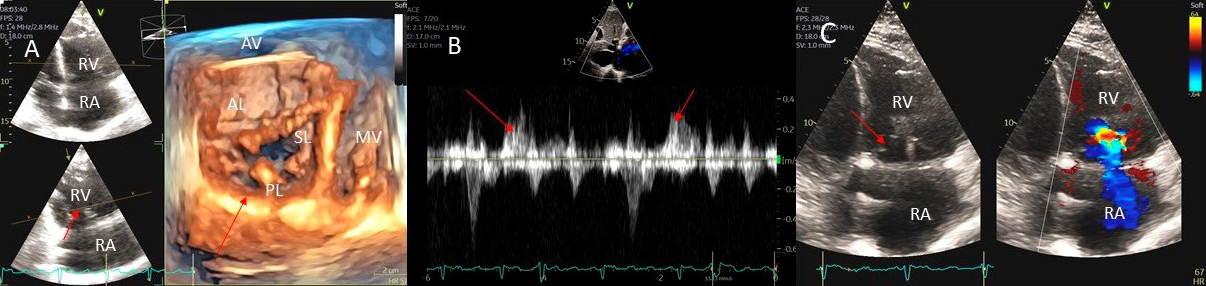

Severe PR also causes RV dilatation and diastolic flattening of the interventricular septum due to volume overload. A normal RV size suggests the absence of chronic severe PR. Carcinoid disease causes thickening and restriction of tricuspid and pulmonic valves leading to valve stenosis and regurgitation. This leads to turbulent forward flow in systole due to varying degrees of pulmonic stenosis and regurgitation due to incomplete closure of the thickened and restricted valve leaflets (Fig. 12).

Fig. 12.Pulmonic valve regurgitation and stenosis. Transthoracic echocardiographic images in a patient with carcinoid syndrome involving the pulmonic valve. Short axis biplane color Doppler views at the cardiac base showing severe pulmonic insufficiency (black asterisks - (A) and turbulent forward flow in systole due to pulmonic stenosis in (B). Three dimensional transthoracic views showing diffusely thickened and restricted pulmonic valve leaflets in systole (white arrow - (C)) and incomplete closure of the thickened pulmonic valve leaflets in diastole (white arrow - (D)) causing severe pulmonic regurgitation.